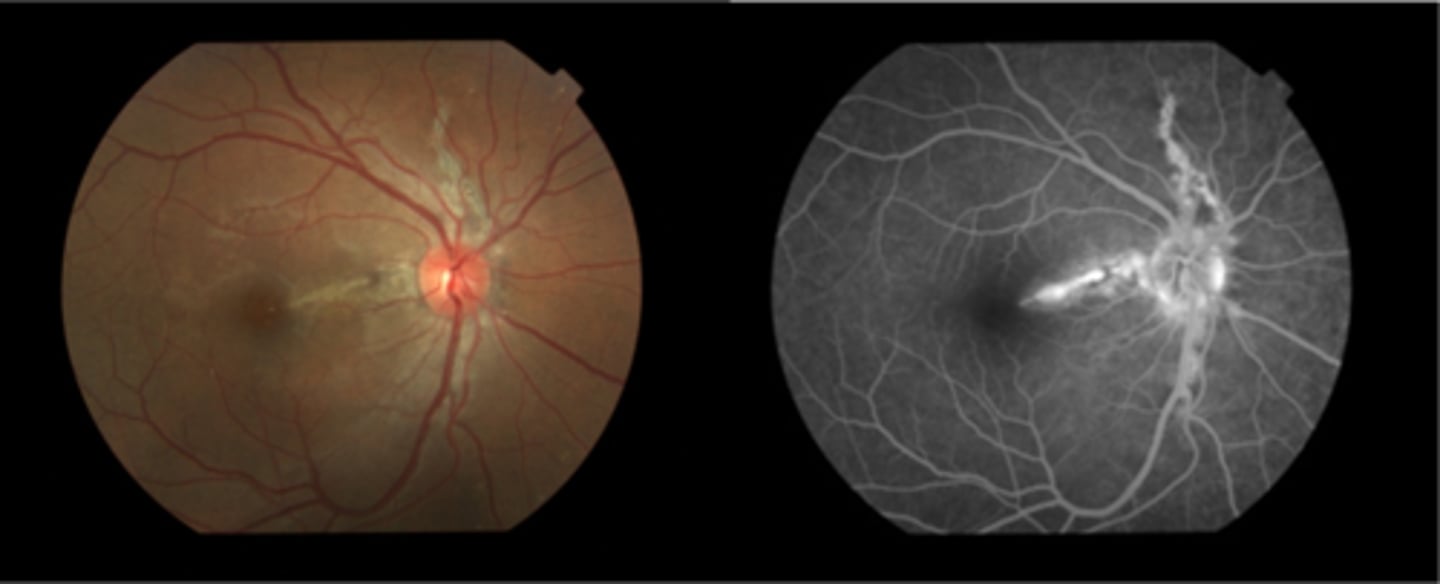

What are angioid streaks and what type of atrophy do they lead to?

breaks in Bruch's membrane in a radiating fashion emanating from the ONH = leads to RPE, PR's, choriocapillaris atrophy

What causes angioid streaks?

weakened, calcified Bruch's membrane, often in connective tissue disease = bilateral

What are the 5 CT diseases associated with angioid streaks?

PEPSI:

Pseudoxanthoma elasticum

Ehlers-Danlos syndrome

Paget's disease (of bone)

Sickle cell disease (and other hemoglobinopathies)

Idiopathic

THINK: Angie likes to drink PEPSI

How do angioid streaks affect VA?

often asymptomatic as does not involve macula

What are 2 possible complications of angioid streaks?

CNV

choroidal rupture

How do we manage angioid streaks?

educate on potential CNV or choroidal rupture, esp with injury = polycarbonate, reduced contact sports

Amsler for home monitoring

refer for CT disease workup if not already diagnosed

How does angioid streaks appear on IVFA?

hyperF bc loss of RPE = can see choroid better

How does angioid streaks appear on FAF?

hypoAF bc RPE loss/damage

What ONH finding is sometimes seen with angioid streaks?

disc drusen